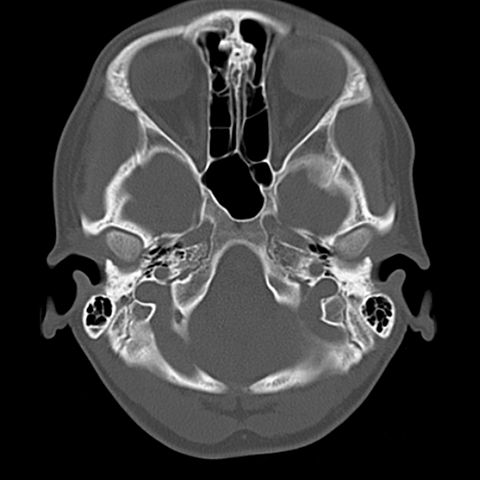

Skull Base [6 of 7]